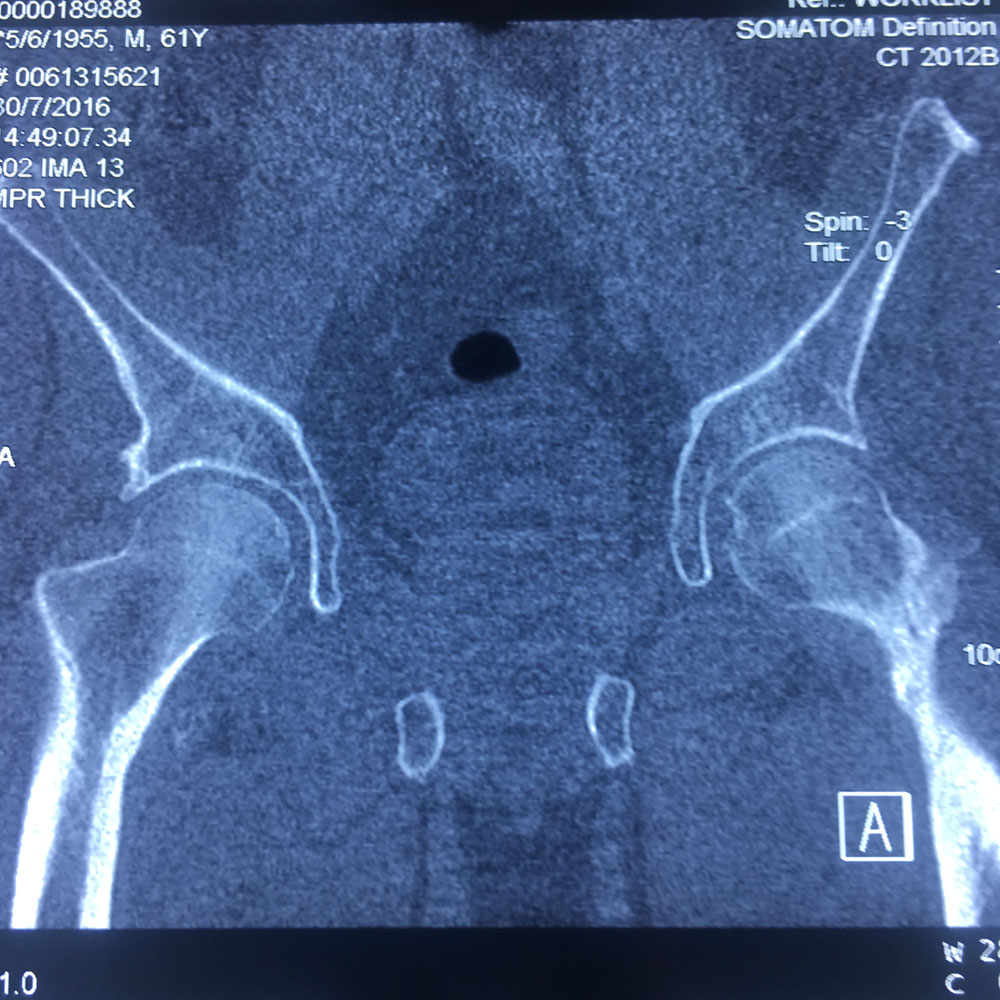

Εικόνα 1(α,β,γ,δ): Οι ακτινογραφίες Face & Profile λεκάνης, ισχίων έδειξαν την ύπαρξη εκφυλιστικών αλλοιώσεων. Ιδιαίτερα στη δεξιά κατ’ ισχίον άρθρωση.

Εικόνα 2 (α,β): Αξονική Τομογραφία της δεξιάς κατ’ ισχίον άρθρωσης

Παρατηρούνται πολλαπλές εκφυλιστικές αλλοιώσεις σε αμφότερες τις κατ’ ισχίον αρθρώσεις, ενώ παρατηρείται κυστική αλλοίωση στη κεφαλή του δεξιού μηριαίου οστού. Ήπιες αλλοιώσεις ιερολαγονίτιδας δεξιά.